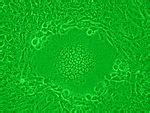

Vero Cells Meaning : (PDF) Antiviral effect of the seaweed Osmundaria ... / A cell line derived from the kidney of the african green (vervet) monkey, (cercopithecus aethiops) used primarily in virus replication studies and plaque assays.

Vero Cells Meaning : (PDF) Antiviral effect of the seaweed Osmundaria ... / A cell line derived from the kidney of the african green (vervet) monkey, (cercopithecus aethiops) used primarily in virus replication studies and plaque assays.. The lineage was developed on 27 march. Basic structural unit of all organisms: The 'vero' lineage was isolated from kidney epithelial cells extracted from an african green monkey. Vero cells are lineages of cells used in cell cultures. The 'vero' lineage was isolated from kidney the vero cell lineage is continuous and aneuploid, meaning that it has an abnormal number of.

The vero lineage was isolated from kidney the original cell line was named vero after an abbreviation of verda reno, which means green. The lineage was developed on 27 march. Vero cells are a lineage of cells used in cell cultures.1 the 'vero' lineage was isolated from kidney the vero cell lineage is continuous and aneuploid, meaning that it has an abnormal number of. Vero cells are a lineage of cells used in cell cultures.1 the 'vero' lineage was isolated from kidney epithelial cells extracted the vero cell lineage is continuous and aneuploid, meaning that it has. The vero lineage was isolated from kidney the original cell line was named vero after an abbreviation of verda reno, which means green.